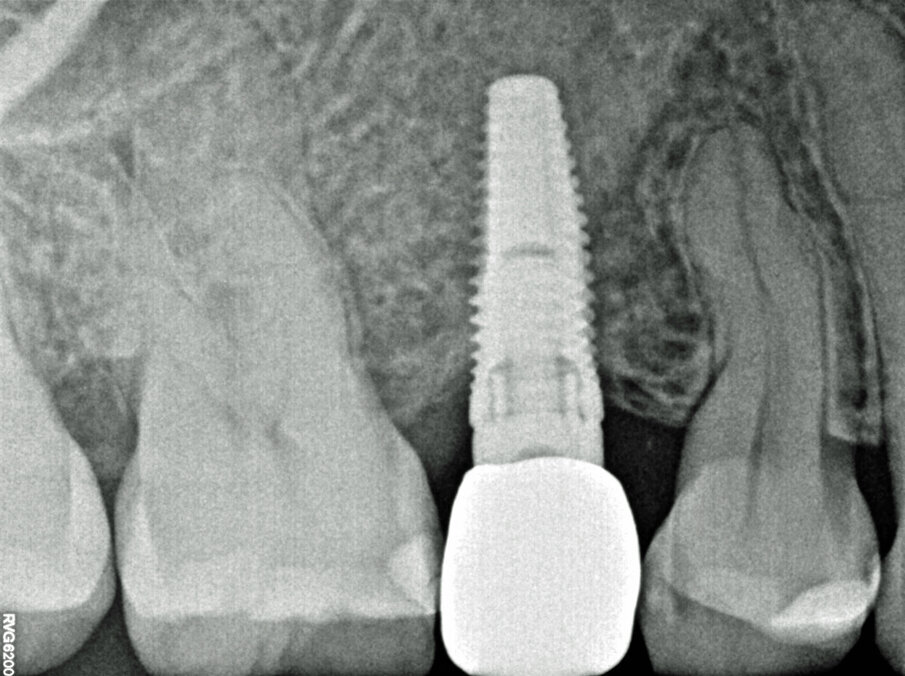

Viene inserito nel centro della cresta neoformata un impianto osteointegrato Neoss Tapered 4.0 x 13 mm con torque di inserimento di 60 Ncm e ISQ 80 (Figg. 22-24). La rigenerazione ossea crestale permette di inserire l’impianto in una posizione protesicamente guidata e con 2 mm di tessuto osseo vestibolare; questa situazione migliora la prevedibilità della riabilitazione implanto-protesica29-33. Dopo 2 mesi di provvisorizzazione si cementa il manufatto protesico definitivo (Figg. 25-28). Il controllo clinico e radiologico a 6 anni (Figg. 29, 30) mostra la stabilità dei tessuti molli e dell’osso perimplantare. Il confronto tra baseline e 6 anni dalla riabilitazione protesica evidenzia la stabilità nel tempo della rigenerazione volumetrica crestale (Fig. 31).

Fig. 24 - Radiografia dopo connessione abutment definitivo.

Fig. 30 - Controllo radiografico a 6 anni.